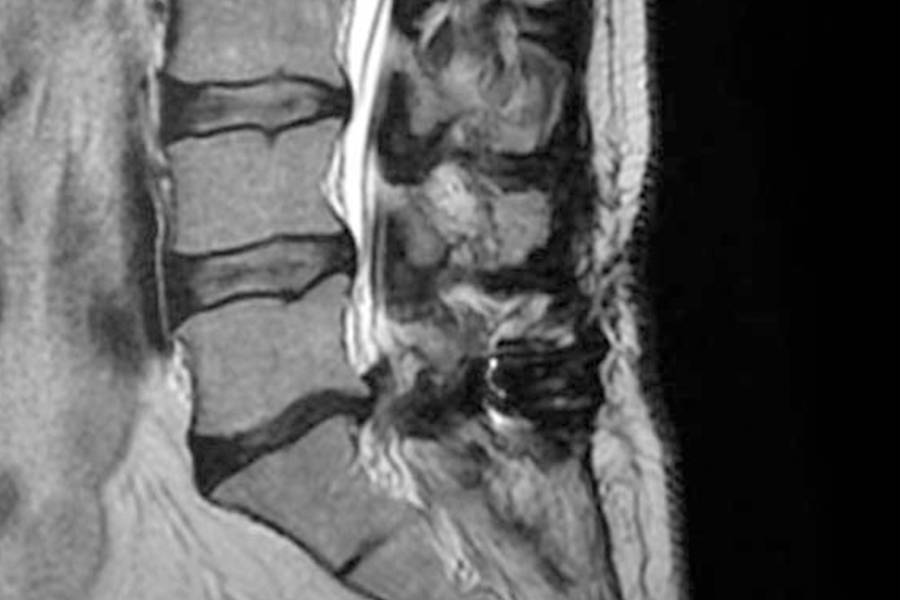

Durante la intervención quirúrgica, se abordarán los dos niveles mediante la técnica de endoscopia de columna.